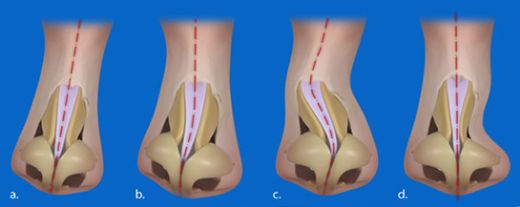

Burun Kıkırdak Eğriliği Belirtileri ve Tedavisi Burun kıkırdak eğriliği, burun septumunun (burun ortasındaki yapı) anormal bir şekilde eğrilmesi veya şekil bozukluğu olarak tanımlanabilir. Bu durum, bireylerin yaşam kalitesini etkileyen ve çeşitli sağlık sorunlarına yol açabilen önemli bir rahatsızlıktır. Burun kıkırdak eğriliği, genellikle doğuştan gelir, ancak travma veya yaralanmalar sonucu da gelişebilir. Burun Kıkırdak Eğriliğinin Belirtileri Burun kıkırdak eğriliği, birçok belirtiyle kendini gösterebilir. Bu belirtiler kişiden kişiye değişebilir, ancak genel olarak aşağıdaki semptomlar sıklıkla görülmektedir:

Tedavi Seçenekleri Burun kıkırdak eğriliği tedavisi, hastanın semptomlarına ve durumun ciddiyetine bağlı olarak değişiklik gösterir. Tedavi yöntemleri şunlardır: